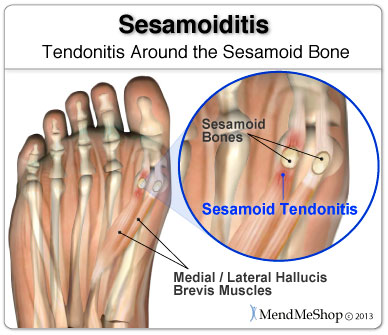

Sesamoiditis Big Toe Joint Pain Ohio Foot Ankle Specialists

Sesamoiditis Symptoms Treatment My FootDr

Sesamoiditis